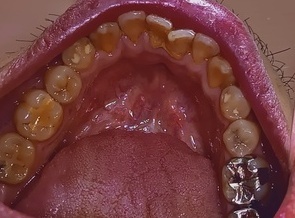

Before(歯石除去前)

「前歯の裏側に歯石があり、前歯の裏側がざらざらすして、ブラッシング時に出血がする」とご相談いただきました。

After(歯石除去後)

可能な範囲で歯石の除去を行い、歯面の改善を確認しました。歯間も開き、健康的な歯列になりました。歯面のざらつきが改善され、ブラッシング時の快適性が向上した仕上がりです。

拝見したところ、下の前歯の裏側に歯石が付着しており、歯と歯の隙間もふさがっている状態でした。